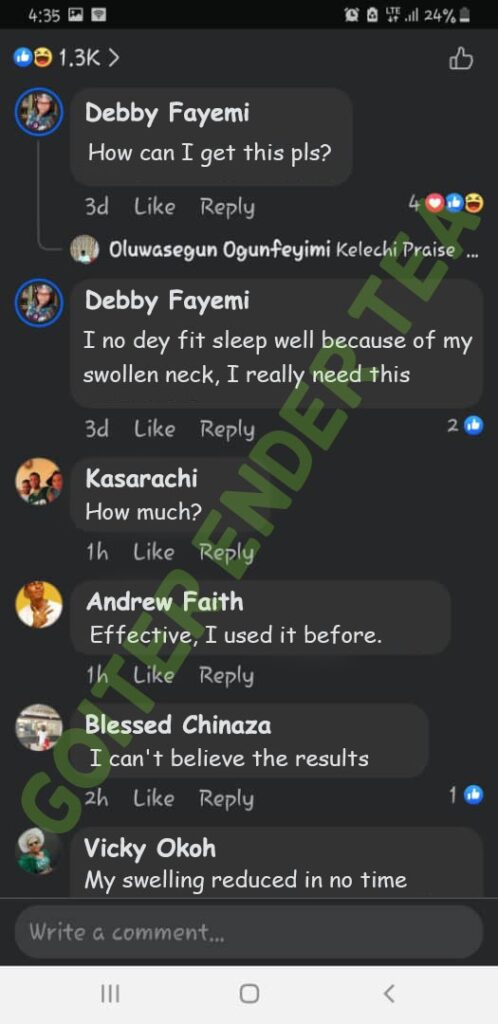

FEW TESTIMONIALS FROM OUR CUSTOMERS

We have sold this product to a lot of people and many of them are calling back to tell us that it worked for them.